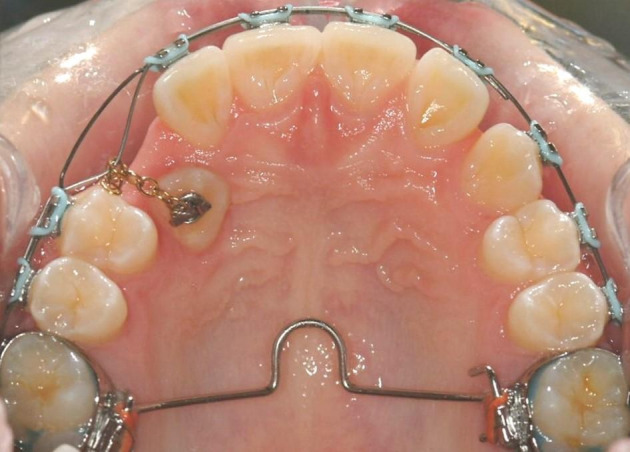

The closed technique involves surgically uncovering the tooth and gluing an attachment onto the exposed tooth, often in the form of a gold chain. The palatal flap is then repositioned and sutured, with the chain exiting through the mucosa. Historically, this could be seen as quite challenging in the surgical theatre setting; however, with the advent of new self‐etch adhesive bonding systems, the bonding technique could be simplified. Shortly after surgery, an orthodontic brace is used to apply gentle forces to bring the canine into its correct position, within the dental arch. The canine then erupts through the mucosa into its correct position (Clark 1971). See Figure 1.

1.

Open technique

The open technique differs slightly. It involves surgically uncovering the canine tooth, as before, but instead of bonding an attachment on the exposed tooth at the time of the surgery, a window of tissue is removed from around the tooth leaving it exposed. A dressing or 'pack' is placed to cover the exposed area. The dressing is removed approximately 10 days later. The tooth is then either left to erupt naturally, or an orthodontic attachment is placed to enable the tooth to be moved, above the gum, into its correct position in line with the rest of the teeth (Lewis 1971). See Figure 2.

2.

Closed technique